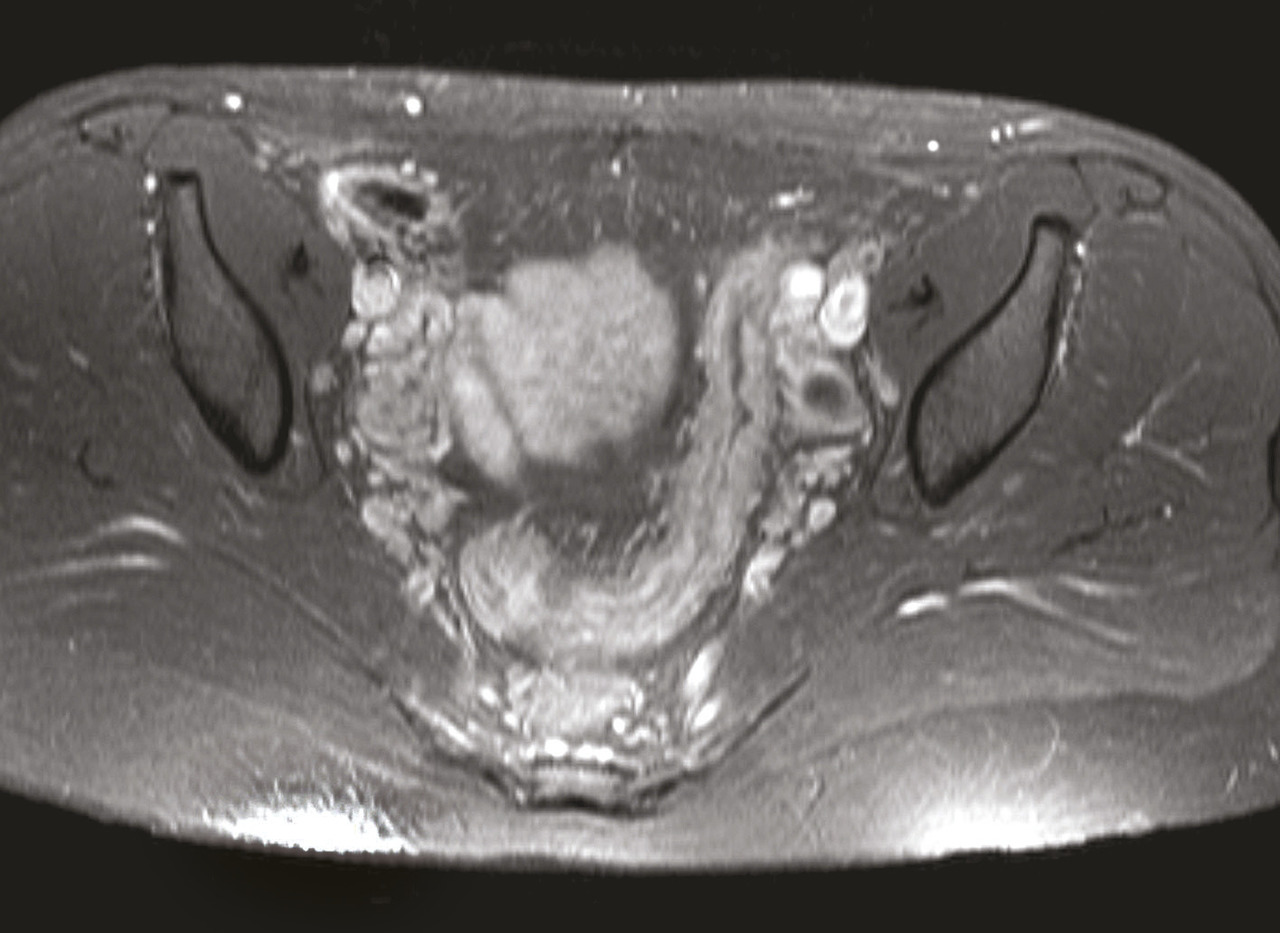

Les thiopurines ont un potentiel carcinogène du fait de lésions irréversibles de l’ADN.34 Le risque de cancer de la peau non mélanocytaire (carcinome basocellulaire et carcinome épidermoïde) sous thiopurines est clairement démontré.35, 36 Ce risque augmente avec l’âge et est particulièrement élevé après 65 ans.35 Point important, il persiste au-delà de l’arrêt du traitement.35 À l’inverse, il ne semble pas exister de sur-risque de mélanomes.37 Récemment, des données issues de la cohorte CESAME ont également montré un sur-risque de cancer du rein et de la vessie,38 particulièrement chez les hommes de plus de 65 ans,38 avec la réserve que le tabagisme n’était pas une variable disponible lors de l’analyse alors qu’il s’agit d’un facteur de risque connu des voies urinaires.39 Chez la femme, il semble également exister un sur-risque de cancer du col utérin.40

L’une des préoccupations majeures concernant les thiopurines est le risque de lymphome, principalement non hodgkinien. Ce risque avait déjà été mis en évidence chez les patients transplantés d’organes solides, avec une implication démontrée du virus d’Epstein-Barr (EBV).41 Ce risque est désormais bien montré dans les MICI, avec un risque de lymphome sous thiopurines multiplié par 5 par rapport aux patients sans traitement.42, 43 Le lymphome T hépatosplénique est un syndrome lymphoprolifératif non induit par l’EBV induit, rare et constamment fatal. Cette pathologie survient dans plus de 90 % des cas chez des hommes, à un âge moyen de 35 ans.44 Dans les 40 cas décrits de lymphome T hépatosplénique chez des patients atteints de MICI, tous étaient traités par thiopurines, associées à un anti-TNF dans la moitié des cas44 (tableau 1 ). C’est pourquoi il est recommandé, si possible, de ne pas poursuivre de combothérapie impliquant un anti-TNF et une thiopurine plus de 2 ans, particulièrement chez les hommes jeunes ou les patients de plus de 65 ans.45 Un risque majoré de syndrome myélodysplasique (incluant les leucémies aiguës myéloblastiques) a également été démontré chez les patients ayant une MICI ayant reçu des thiopurines avec une incidence multipliée par 7.46 Des chiffres identiques ont été notés chez des patients traités par azathioprine pour diverses maladies auto-immunes47 ainsi que chez les trans- plantés d’organes solides.48 Il a été démontré chez l’enfant que ce risque se majore avec la durée d’exposition.49 Bien que ce sur-risque semble persister après l’arrêt du traitement, le risque absolu par individu reste faible, de l’ordre de 1 pour 10 000.46 De très rares cas de syndrome d’activation macrophagique ont également été décrits sous thiopurines, potentiellement gravissimes.50